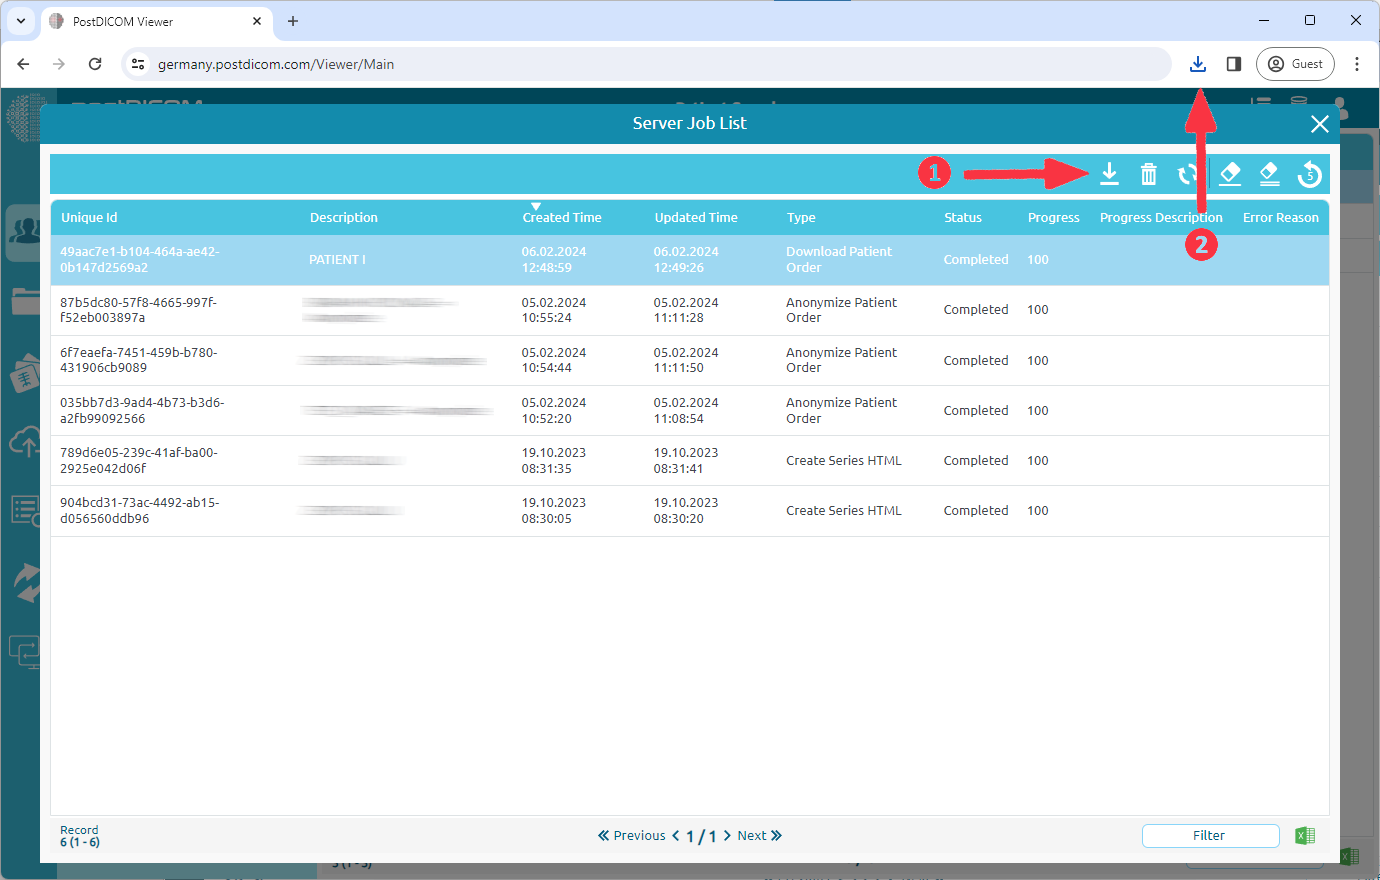

A job which type is 'Download Patient Order' has been added to your job list. When the job is complete, the download will start automatically. If it does not start, you can click the 'Download' button (1).

Click the folder icon (1) to view downloads folder.